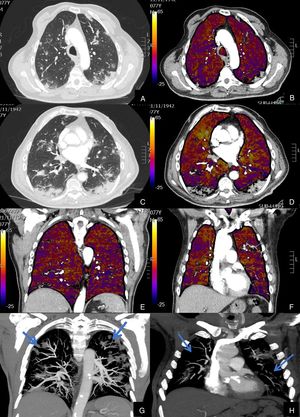

Paciente con COVID-19 que persiste con desaturación a pesar de mejoría clínica.

Imágenes axiales de la angiografía pulmonar con TC y mapa de yodo con ventana de pulmón (A, C, E) desde cayado hasta lóbulos inferiores y su correlación con las imágenes del mapa de yodo (B, D, F).

Parénquima con extensa afectación en vidrio deslustrado de predominio subpleural con consolidación de pequeño tamaño en LID, sin TEP visible, con áreas parcheadas de hipoperfusión (zonas azules) en el mapa de yodo, de predominio periférico, que coinciden con las zonas en vidrio deslustrado.